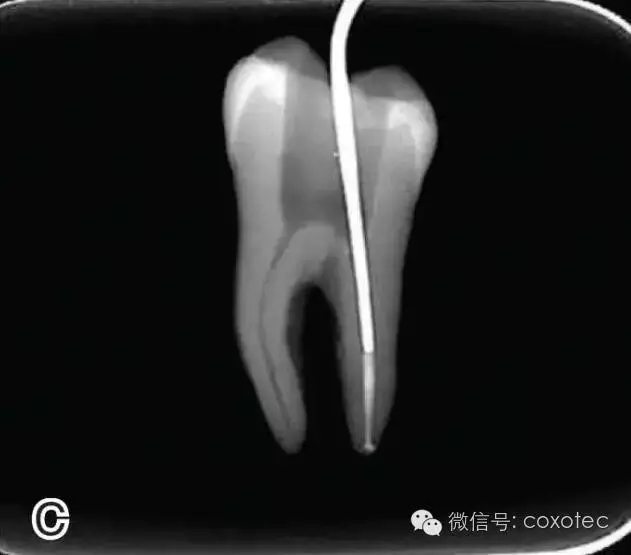

將攜熱器工作尖向根尖加熱加壓至距參照點(diǎn)約2 mm處,關(guān)閉加熱器,保持根向壓力,使工作尖前進(jìn)到參照點(diǎn)處。保持加壓狀態(tài)10秒鐘(圖6)。

圖6 連續(xù)加壓,A、B.?dāng)y熱器加壓